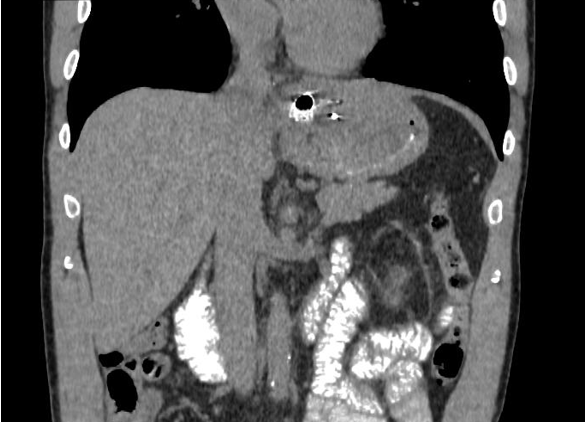

При контрольной рентгеноскопии на вторые сутки наблюдения отмечено уменьшение полости кисты, без затеков контрастного вещества, раскрытие стента удовлетворительное, до 50 % на уровне талии. Талия по центру. Течение послеоперационного периода гладкое, однако отмечалось наличие синхронного трепетания диафрагмы (singultus) вследствие раздражения нитиноловым стентом. По результатам контрольной компьютерной томографии органов брюшной полости с контрастированием, выполненной на третьи сутки после операции, стент определялся на уровне кардиального отдела желудка. Ранее выявленный жидкостной коллектор достоверно не визуализировался. Затеков ранее принятого контрастного йодсодержащего препарата за пределы стента не отмечено. Результаты контрольной компьютерной томографии представлены на рисунках 3 и 4.

Рис. 3. Компьютерная томограмма с пероральным и внутривенным контрастным усилением, пациент К., 54 года, фронтальный срез. 1 – стент на уровне кардиального отдела желудка

Fig. 3. Computed tomography with oral and intravenous contrast enhancement, patient K., 54 years old, frontal section. 1 – stent at the level of the cardiac part of the stomach